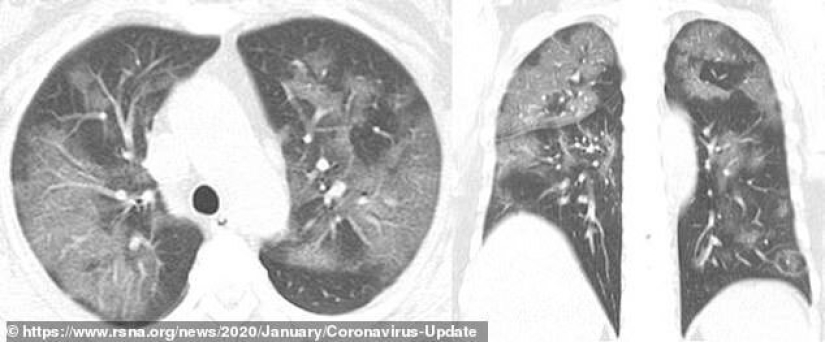

Esta es una instantánea de los pulmones de una mujer de 45 años de Sichuan, examinada después de regresar de Japón y diagnosticada como portadora del virus. La imagen muestra una serie de formaciones similares, pero aquí se concentran en el lóbulo superior del pulmón izquierdo.